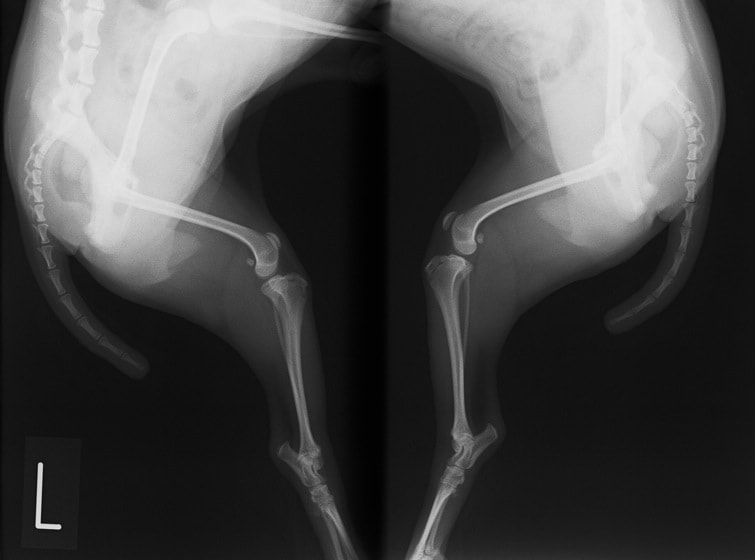

■ 症例20 ポメラニアン 8ヶ月 1.8kg

左右膝蓋骨脱臼 グレードⅢ

2ヶ月前から間欠的跛行が認められ、両膝の膝蓋骨脱臼整復術を行った。

手技は縫工筋及び内側広筋の解放、脛骨粗面の外側転位、滑車ブロック形造溝術、内外側関節包の縫縮を選択し実施した。

右側の膝蓋骨脱臼は上記手技で整復されたものの、左側はそれのみでは膝蓋骨が浮く様子が認められた。その為、PDS縫合糸にて膝蓋靱帯を1糸のみ縫合し、靱帯の縫縮を行った。

膝蓋骨脱臼は膝関節における膝蓋骨の内外側の脱臼と定義されるが、時として単純な内外の脱臼ではなく、膝蓋骨が大きく前方に浮き上がるように脱臼する場合がある。特にトイプードルやポメラニアンといった犬種に多く認められる。

内側脱臼に加えて前方への浮き上がりを矯正する為に、従来より脛骨粗面転移により膝蓋靭帯を外方と下方に引っ張り、固定する方法を選択する。膝蓋骨の前方への浮き上がりが軽度の場合は、従来法ではなく関節包の縫縮で対応していた。しかし、一部の症例で膝蓋骨の動きが悪くなり伸展機構が円滑に機能せずロボット様歩行になるケースがあった。

その為、膝蓋靭帯自体を縫縮する方法を採用した。この方法により、膝関節の伸展機構を妨げず膝蓋骨の軽度の浮きを矯正することが可能となった。

本症例の経過は良好である